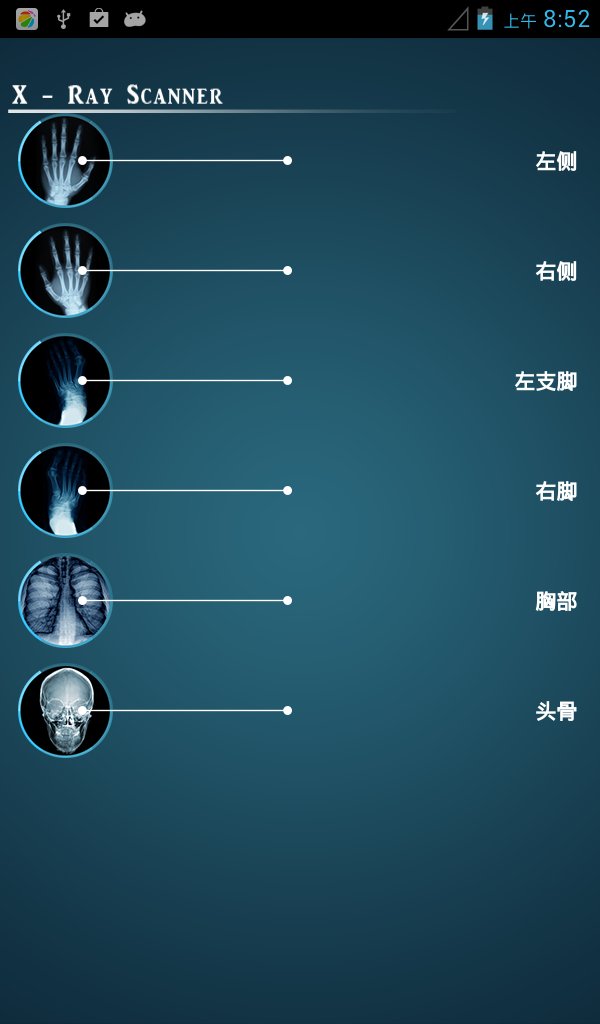

拍摄照片和视频

- 允许访问摄像头进行拍照